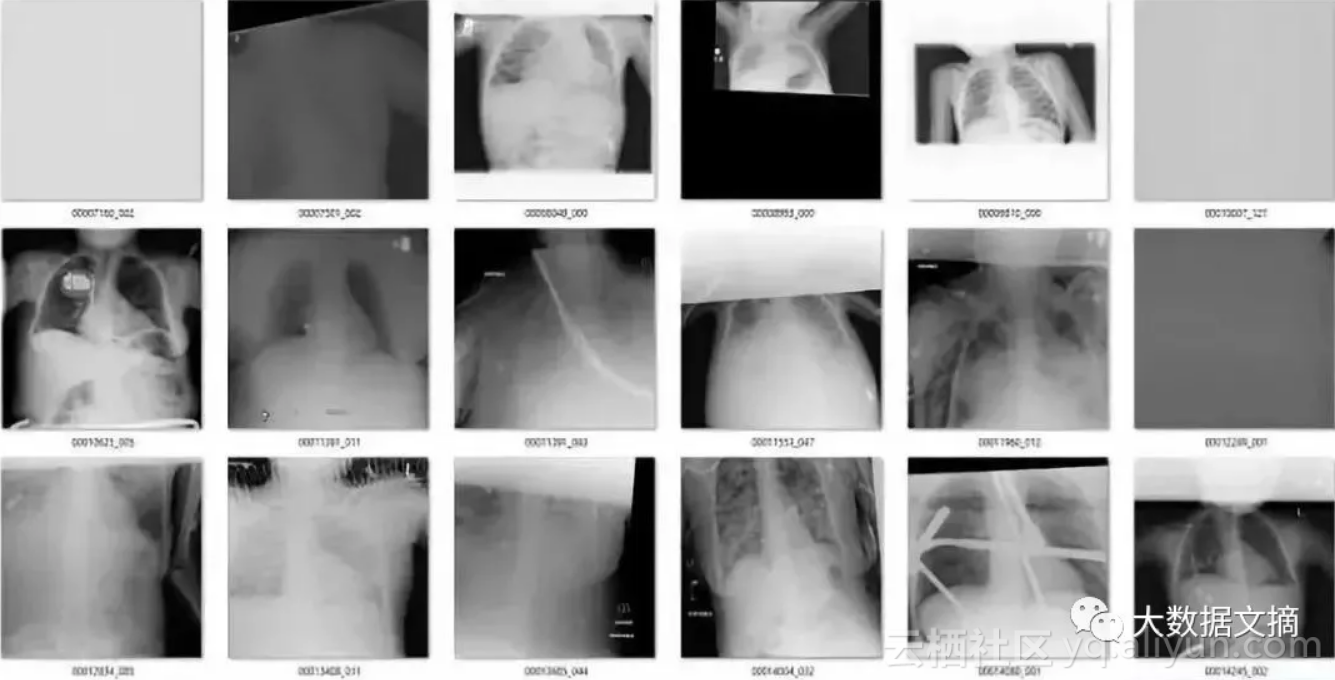

为了说明这一点,我们来看一个来自CXR14的简单例子。在数据集中的正常胸部X射线中,有一些图像经过旋转(这些旋转并未标识在标签中,因此我们不知道哪些是旋转过的)。它们有可能被左右旋转了90度,或180度(颠倒)。

在旋转和竖直胸部X射线之间的差异真的是令人尴尬的简单。

答案是:不难!在视觉上,异常图片与正常图片完全不同。你可以使用一个简单的可视规则,比如说“肩膀应该高于心脏”,然后你就会得到所有正确的结果。鉴于解剖学非常稳定,所有人都有肩膀和心脏,这应该是卷积网络的可以学习的规则。

该模型一共标记出了171个“旋转”的图像。有趣的是,它实际上作为一个“异常”检测器,识别出许多在非胸部X光的图像。这也不难理解,因为这个模型可能是在学习解剖学的标志。任何异常的东西,如旋转的图像或者是其他身体部位的X射线图像,都不具有正常图片应有的特征。真是意外收获!

在171个被标记为“旋转“的图像中,有51个是实际上旋转过的正面胸部X射线图像。鉴于图片旋转发生的概率非常低(120,000个案例中有51个),这已经是极低的假阳性率。

在余下的120个图像中,56个并不是正面胸片。其中主要包括了侧面胸片和腹部X光片,这也是我想要清理出去的异常图片。

那么其余的呢?有一些是经过混合的缩小图像(它们有着黑色或白色的大边界),因为过度曝光而变淡的图像(其中有一些图像整体都是灰色的),还有像素颜色完全翻转的图像等等。

总而言之,大约有10张X光图我认为是“假阳性”(它们其实是我需要的正常的前胸正面X光图)。还有一点很幸运,我们的模型检测出“坏图”的数量只有171张,如果我们想要检查每张图并手动改正模型判断错误的图片,也很容易办到。